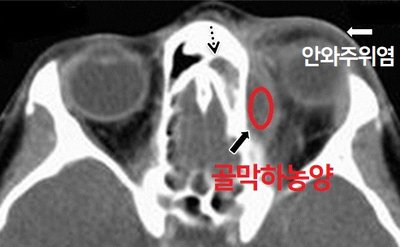

안와내 합병증의 유형 합병증의 진행 과정과 염증의 파급 정도에 따라 안와 주위염, 안와 봉와직염, 골막하 농양, 악와 농양, 해면 정맥동 혈전, 안와첨 증후군으로 구분합니다.

안와주위염 안와주위염은 염증이 안와격막 전방에 한정되어 있어 전체 안와내 합병증의 80% 이상을 차지하고 있습니다.위의 사진과 같이 안검의 종창, 홍반이 나타납니다.

골막하농양의 CT 영상골막하농양은 안와를 둘러싸고 있는 골막과 부비동 골벽 사이의 농양으로 골막하농양이 안와내측에 농양을 형성하면 안와농양이 됩니다.증상은 안와직염과 유사하며 안근, 시신경 손상이 크고 시력 소실을 유발할 수 있습니다.